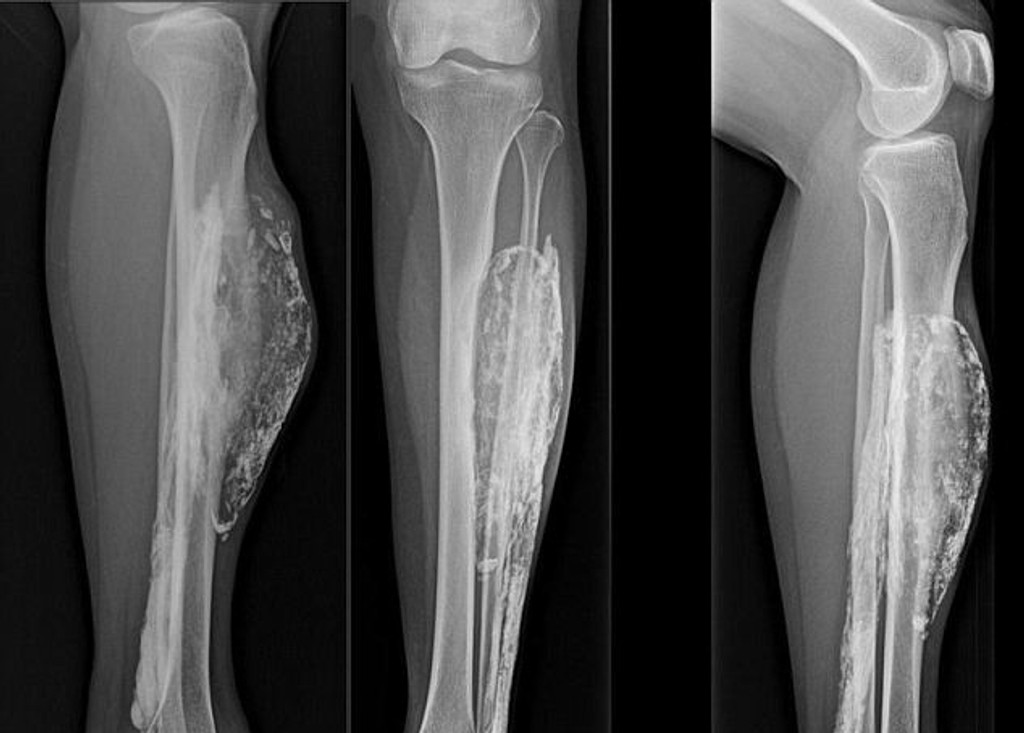

Noha pohrýzenej Thajčanky

Zdroj: dailymail.co.uk

Dnes jej diagnostikovali kompartment syndróm.

Ženu z Thajska pohrýzol had, keď mala 14 rokov. Malajská vretenica ju do nohy uhryzla tak silno, že jej prerazila kožu. Myslela si, že to nič nie je. Avšak pred desiatimi rokmi zistila, že ju noha bolí a niečo jej tam rastie. Thajčanka má teraz 66 rokov a viac ako 50 rokov jej v nohe vyrastala obrovská hmota.

Lekári jej spravili röntgen a diagnostikovali kompartment syndróm. Ochorenie nie je nič nezvyčajné, avšak u ženy rástol neuveriteľných 52 rokov. Tento syndróm je stav, pri ktorom zvýšený tkanivový tlak v uzavretom priestore spôsobuje poruchu cirkulácie a poškodenie svalov, nervov a ostatných zložiek. Aj keď s komplikáciami, hmotu jej chirurgicky odstránili.